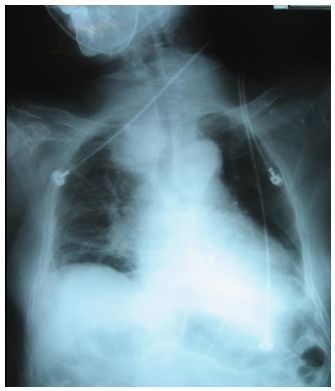

15. 李先生,70歲,罹甲狀腺癌,身體檢查時呈現呼吸喘、急促及窘迫,胸部X光(如附圖), 聽診時最可能發現下列何種狀況? (A) crackles (B) mediastinal crunch(Hamman’s sign) (C) stridor (D) pleural friction rub